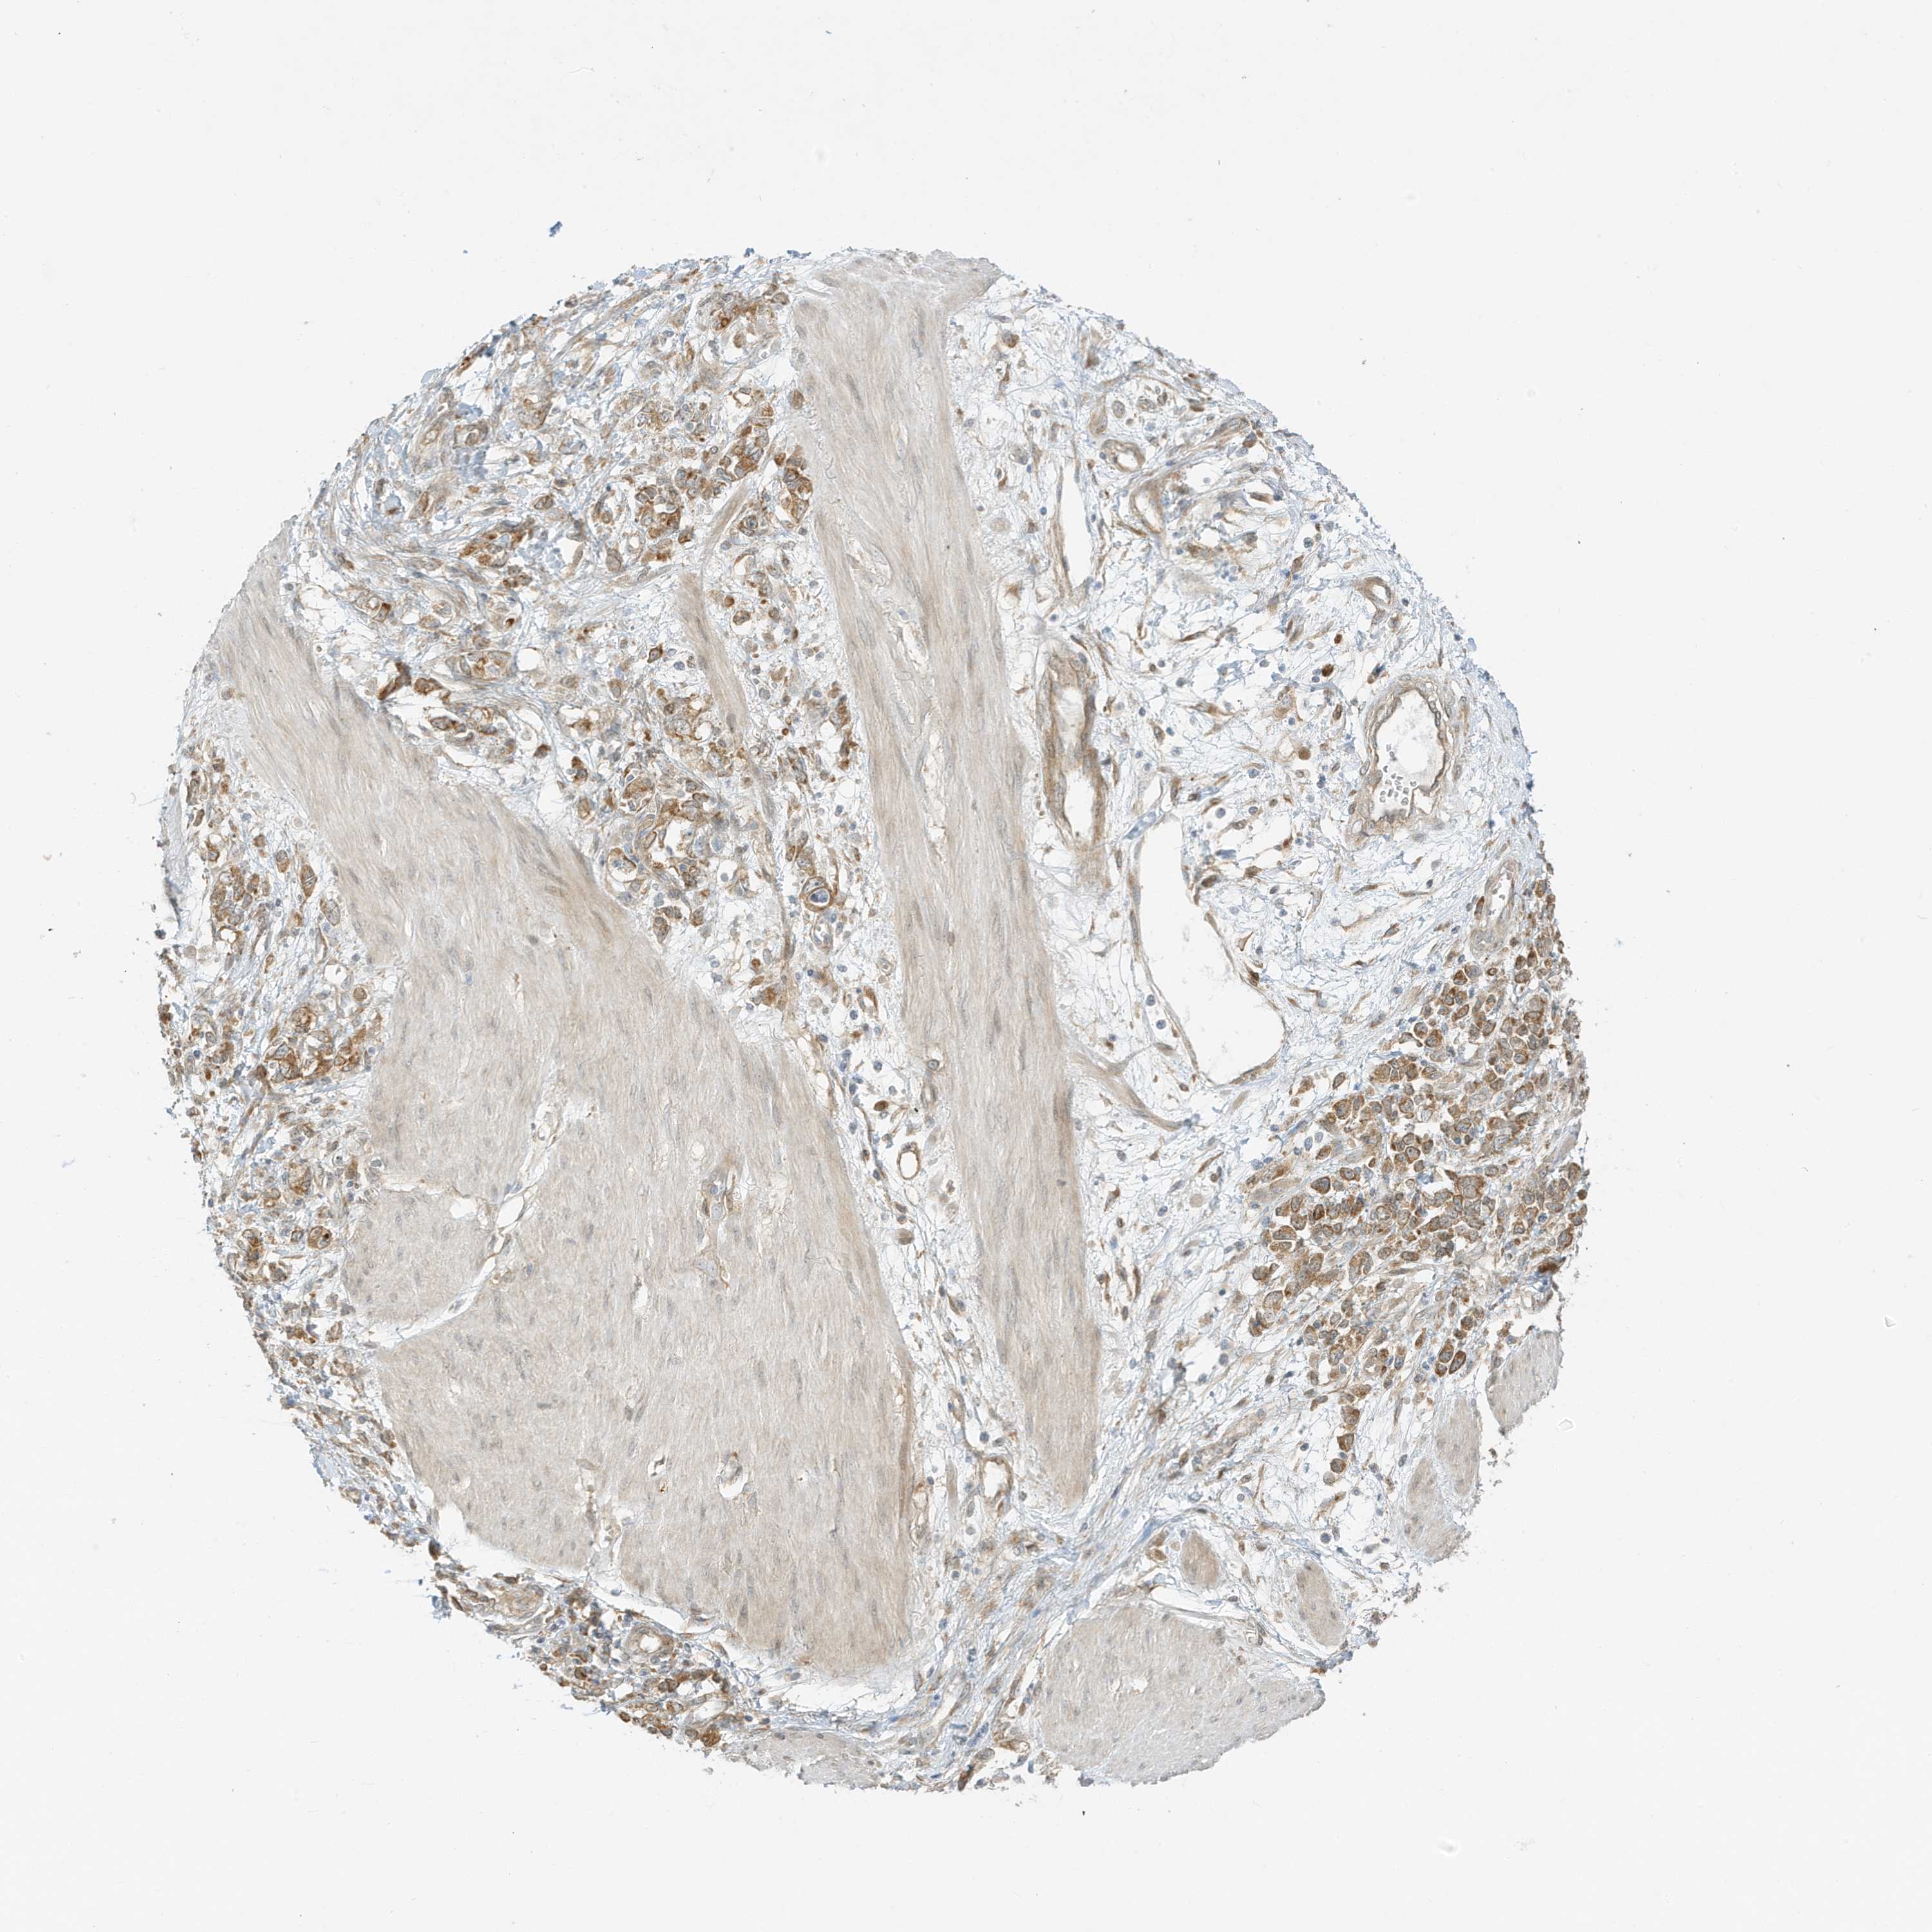

STOMACH CANCER - Protein expressioni

A mouse-over function shows sample information and annotation data. Click on an image to view it in a full screen mode. Samples can be filtered based on level of antibody staining by selecting one or several of the following categories: high, medium, low and not detected. The assay and annotation is described here.

Antibody stainingi

Antibody staining in the annotated cell types in the current human tissue is reported as not detected, low, medium, or high, based on conventional immunohistochemistry profiling in selected tissues. This score is based on the combination of the staining intensity and fraction of stained cells.

Each image is clickable and will lead to virtual microscopy that enables deeper exploration of all samples and also displays staining intensity scores, fraction scores and subcellular localization as well as patient and tissue information for each sample.

Antibody HPA035079

Staining

High

Medium

Low

Not detected

Intensity

Strong

Moderate

Weak

Negative

Quantity

>75%

75%-25%

<25%

None

Location

Nuclear

Cytoplasmic/membranous

Cytoplasmic/membranous,nuclear

Adenocarcinoma, NOS